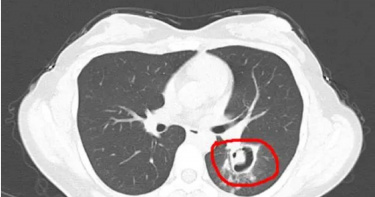

進行打掃工作,也要特別注意。中國浙江杭州有一名沈姓女子,趁著天氣好整理家中衣櫃,沒想到隨後出現發燒、咳嗽等症狀,以為是累到病倒,就醫卻檢查出肺部「發霉」了,只因為忽略了一個細節,而讓細菌有機可乘。根據《潮新聞》報導,沈女到醫院就診,主訴全身不舒服,發燒到40度,還伴隨咳嗽,並提到在換季整理衣櫃時,發現衣櫃長了霉斑,因此特地做了清理,但當下沒有戴口罩。醫師了解情況後,做了支氣管鏡檢查及肺泡灌洗液病原體檢測,結果發現氣道壁上有大量白色菌斑,也是造成沈女高燒、咳嗽的元兇——肺部曲霉菌病,好在經過治療後病情穩定,已經康復出院。沈女感染肺部曲霉菌病。(圖/翻攝自潮新聞)據了解,麴黴屬(又稱麴菌屬)主要以枯死的植物、動物的排泄物及動物屍體為營養源,潮濕環境下容易滋生,家中洗手間地磚、牆縫等地方都可能是其溫床,在溫度20~30度、濕度80%以上的條件最容易繁殖,而長時間未清理的空調,內部也容易積累黴菌。假如感染麴黴屬,常見症狀包括持續高燒不退,服藥也難有明顯效果;咳嗽症狀不斷加重,還可能伴有胸痛、呼吸困難;咳出的痰液中帶有血絲或呈現棕褐色;不只如此,還可能出現鼻塞、流膿鼻涕、臉部疼痛等鼻竇炎症狀,嚴重時可能發生呼吸衰竭甚至危及生命。那麼要如何預防?最有效的除霉方法是開窗通風,也可以開除濕降低屋內濕度,清洗黴菌時要注意戴口罩和手套,以免吸入而引發疾病。另外,還需視情況戴上護目鏡,以防清潔劑濺到眼睛,造成眼部受傷。如果出現持續高燒和反覆咳嗽、咳痰、氣喘等症狀,經治療但效果不佳時,建議可檢查確認是否感染肺部曲霉菌病。

中國一名男子日前因為不斷咳嗽,吃止咳藥後咳嗽不但沒減輕,還兩眼充血,因此到醫院看診。沒想到,經過醫生問診後,發現他因為有聞穿過的襪子的習慣,導致他肺部感染,才會出現這樣的情況。根據陸媒綜合報導,中國重慶一名男子日前因為不斷咳嗽,吃止咳藥後咳嗽不但沒減輕,還兩眼充血,就到當地西南醫院就診。經過醫生進行CT、核磁等檢查後,發現男子右下肺出現斑塊影,並有空洞形成,確診由曲霉菌感染導致的肺部真菌病。後續經過醫生問診發現,男子居住地方的空氣並不算很流通。此外,男子還有一個習慣,就是每天脫掉襪子後,都會習慣性聞一下。之後,醫生對男子的襪子進行了化驗,果真在上面發現了曲霉菌,而就是每天聞襪子的習慣,才會導致他的肺部感染。最終男子接受了藥物、霧化等治療,症狀明顯好轉,目前已出院。對此,呼吸內科副主任羅虎也解釋「穿過的襪子上主要殘留有汗液、鹽分、尿素等,長時間穿鞋形成密閉、潮濕、溫暖的空間,容易滋生真菌。如果去聞、猛吸附著了真菌的襪子,真菌就可能通過口腔、鼻腔進入下呼吸道。如果機體免疫功能低下,就有可能引發真菌性肺炎等疾病。」

中國杭州1名王姓女子在1個月前,發現家具上發霉,便開始動手清潔,豈料竟出現咳嗽、疲倦,而後還燒到40度,經醫生檢查,她的肺部竟然「發黴」了,肺部長出了一個個小樹芽,化驗後確認是曲霉菌。至於為何黴菌會長進肺部,則是因為她在打掃時忘記戴口罩和手套,才會誤吸。據杭州日報報導,王女在1個月前發現家中衣櫃發霉,便開始動手清潔,但卻沒有做好相關防護,打掃後她出現陣發性咳嗽、疲倦,起初程度比較輕微,她以為是普通的感冒,沒想到卻反覆高燒,最高燒到了40度,朋友一看不妙,就趕緊將她送往附近的醫院。為了進一步確認病情,醫師為王女做了纖維支氣管鏡檢查,果然發現氣道壁上有著大量白色菌斑,化驗後確認是曲霉菌。醫師判斷,這些灰塵很有可能混入了各種黴菌,且王女平常喜歡開窗通風,正值5月氣候回暖、陰雨不斷,空氣潮濕是利於黴菌生長的天然條件,黴菌在人體內可引發肺部、口腔、皮膚甚至全身性感染。醫生也提醒,大家要做好以下幾點:一、做好居家清潔工作定期晾曬棉被,勤打掃,及時清理發黴物品。可用消毒水,如3%的過氧化氫、蘇打水,或1:1調配的水和白醋進行清潔,也可以對書籍、地毯等進行陽光晾曬。打掃時要戴口罩和手套,以免誤吸。二、室內注意通風黴菌喜歡在潮濕的環境中生長,因此家中或辦公室要注意通風,尤其在梅雨季節。在潮濕重災區可以掛除濕小物,也可以使用除濕機或空調,使室內濕度保持在40%至50%之間。盡量減少室內綠植栽培,避免土壤中的黴菌滋生。三、不要囤積過多的食物一旦發現食物發黴要及時丟掉,隔夜的食物也不要吃。四、提高自身的免疫力多參與體育鍛煉,保持充足的睡眠,保持樂觀的情緒,補充優質蛋白質。